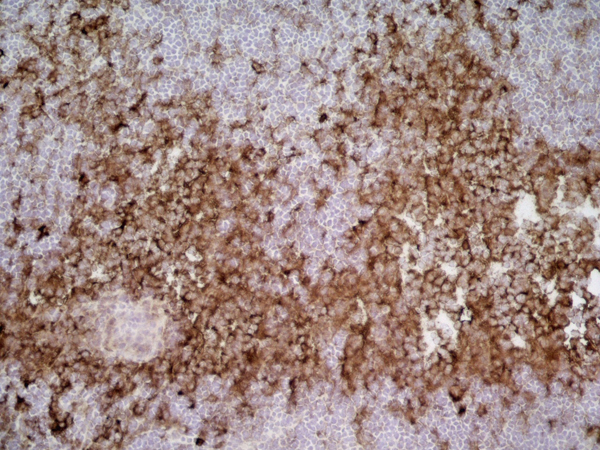

K2, Polyclonal Antibody (Cat# AAA14536)

Orexin receptor 1, Polyclonal Antibody (Cat# AAA13669)

GPR182 / ADMR, Polyclonal Antibody (Cat# AAA12333)